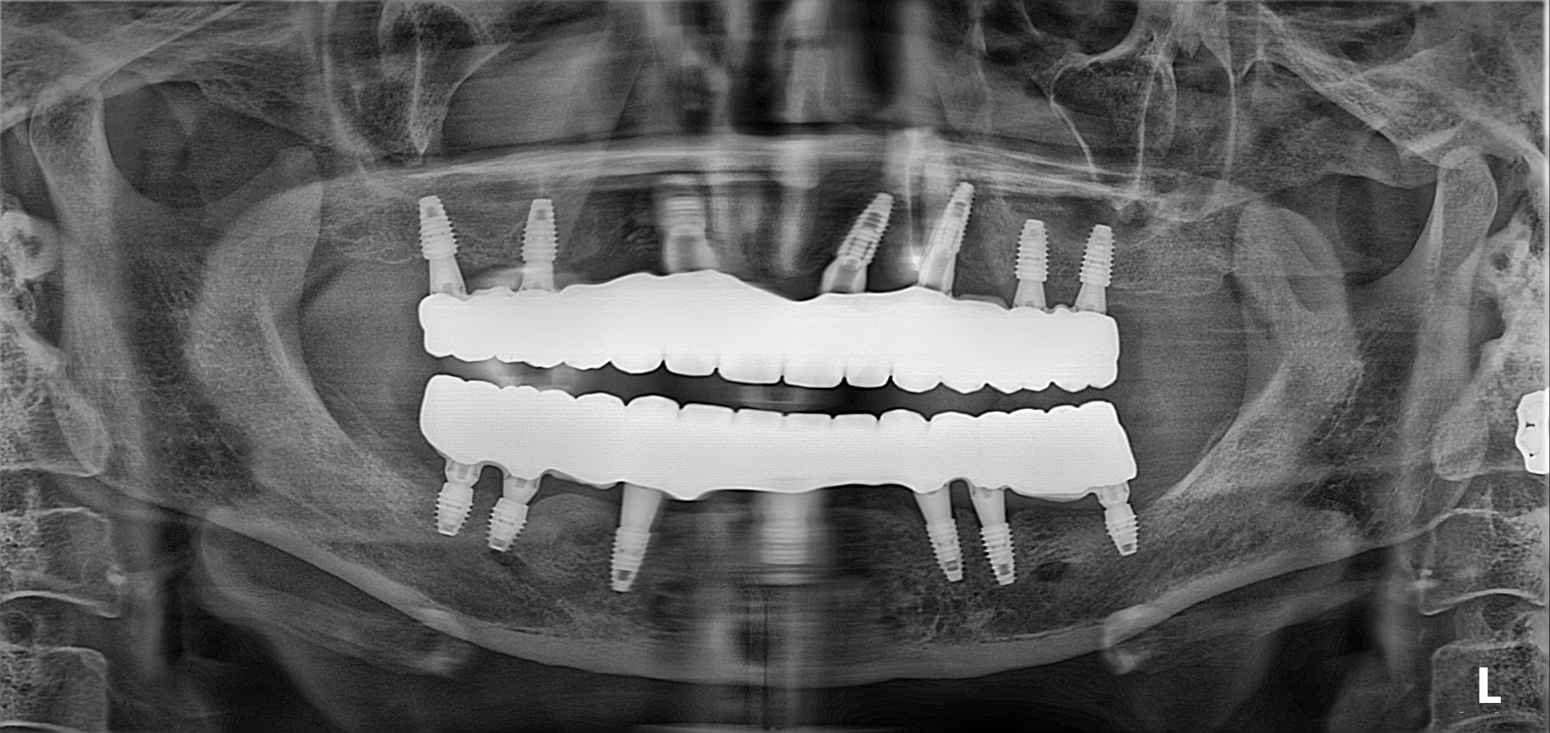

31. Full-Arch All-on-6 Rehabilitation: Overcoming Severe Bone Atrophy and Flabby Tissue

Transitioning from unstable, ill-fitting dentures to definitive fixed stability in a female patient in her 60s. A comprehensive Maxillary and Mandibular All-on-6 reconstruction to resolve chronic "Flabby Gum" syndrome.